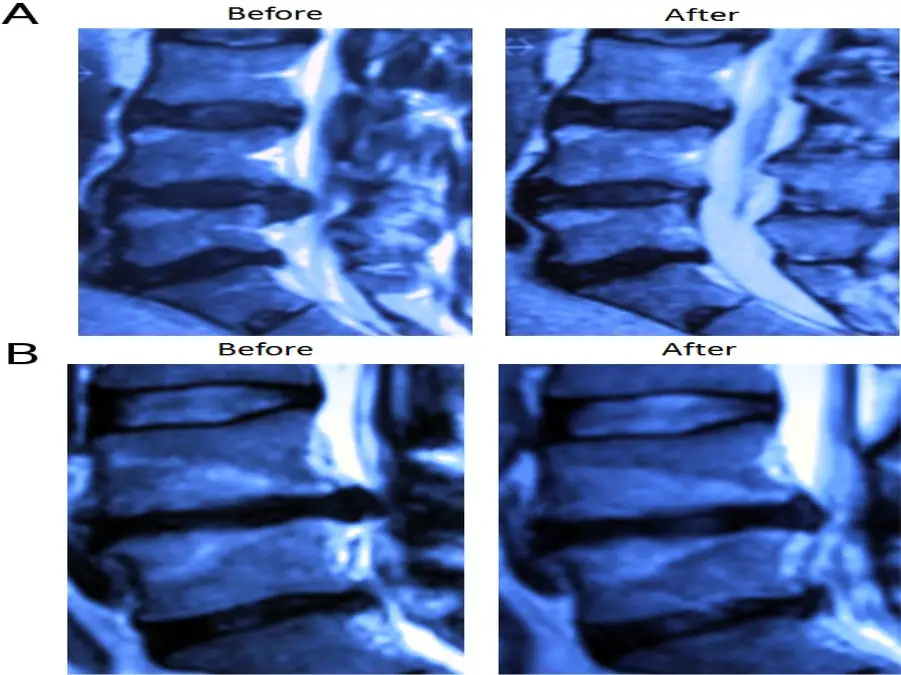

Oxygen-ozone therapy for herniated lumbar disc in patients with subacute partial motor weakness due to nerve root compression

درمان اکسیژن-ازون برای فتق دیسک کمر در بیماران مبتلا به ضعف حرکتی نسبی تحت حاد ناشی از فشردگی ریشه عصبی

بررسی سیستماتیک دیگری که بر فتق دیسک گردن متمرکز شده بود، نتایج مثبت مشابهی را با اوزون درمانی پیدا کرد. بر اساس چکیده ای از PubMed، بیمارانی که تحت درمان با اوزون قرار گرفتند، تسکین قابل توجهی از علائم خود از جمله کاهش شدت درد و بهبود دامنه حرکتی را تجربه کردند. مطالعه متن کامل توسط و همکاران. بینش بیشتری در مورد اثربخشی این درمان ارائه می دهد. این یافته ها نشان می دهد که اوزون درمانی ممکن است جایگزین موثری برای کمردرد مربوط به فتق دیسک کمر و گردن باشد.

معرفی اوزون با کاهش التهاب و بهبود در دیسک آسیب دیده به کاهش درد کمک می کند. این درمان موثر ثابت شده است و توسط مطالعات تحقیقاتی پشتیبانی می شود. اوزون درمانی یک درمان امیدوارکننده برای تسکین درد و بهبود دیسک است. اوزون درمانی یک درمان امیدوارکننده برای تسکین درد و بهبود دیسک است. این تکنیک پزشکی احیا کننده اکسیژن رسانی را تحریک می کند و تعادل ردوکس را بهبود می بخشد و باعث بهبودی می شود.

اوزون درمانی دیسک کمر یک گاز طبیعی است که در هر مولکول از سه اتم اکسیژن تشکیل شده است. هنگامی که به طور مستقیم به دیسک فتق تزریق می شود، حجم قسمت فتق دیسک را کاهش می دهد. همانطور که بخش فتق حجم دیسک کاهش می یابد، فشار روی اعصاب نیز کاهش می یابد که به نوبه خود، میزان درد را کاهش می دهد.

برخلاف جراحی ستون فقرات، روش تزریق اوزون به داخل دیسکال باعث آسیب فیزیکی به ستون فقرات نمی شود. همچنین این روش آناتومی دیسک را تغییر نمی دهد، بنابراین احتمال انحطاط دیسک در آینده را افزایش نمی دهد. این روش در واقع سلامت طولانی مدت دیسک را بهبود می بخشد. در مقابل، تمام روشهای جراحی – از جمله عملهای کم تهاجمی مانند دیسککتومی آندوسکوپی، میکرودیسککتومی یا جراحی لیزری – شامل برداشتن یا تبخیر بخشی از دیسک آسیبدیده است که ارتفاع و یکپارچگی دیسک را کاهش میدهد.